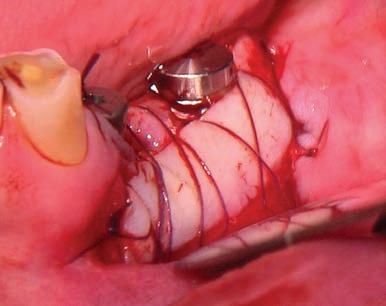

The third step of the treatment consisted of the crown lengthening, necessary to expose an adequate part of the root to obtain, after healing, the correct adhesion of the composite for the pre-prosthetic restoration and the successive prosthetic rehabilitation.

After the surgical flap elevation of the tissue and the bone remodeling, the flap was repositioned apically and sutured with a vertical mattress suture anchored in the periosteum (Figs. 5-6). The suture was removed after 7 days (Fig. 7).

glass fibre Figure 3: Root canal therapy completed under proper isolation. Figure 4: Radiography of completed root canal therapy and reconstruction made completely in glass hybrid cement. Figure 5: Clinical crown lengthening with a minimally invasive technique without mesial and distal discharges. Note the proximity of the reconstruction in glass hybrid material to the mesial bone ridge. Figure 6: Suture at the end of surgical therapy. It was left in place for 7 days Figure 7: Suture removal at 7 days. Post-surgical edema is still present.